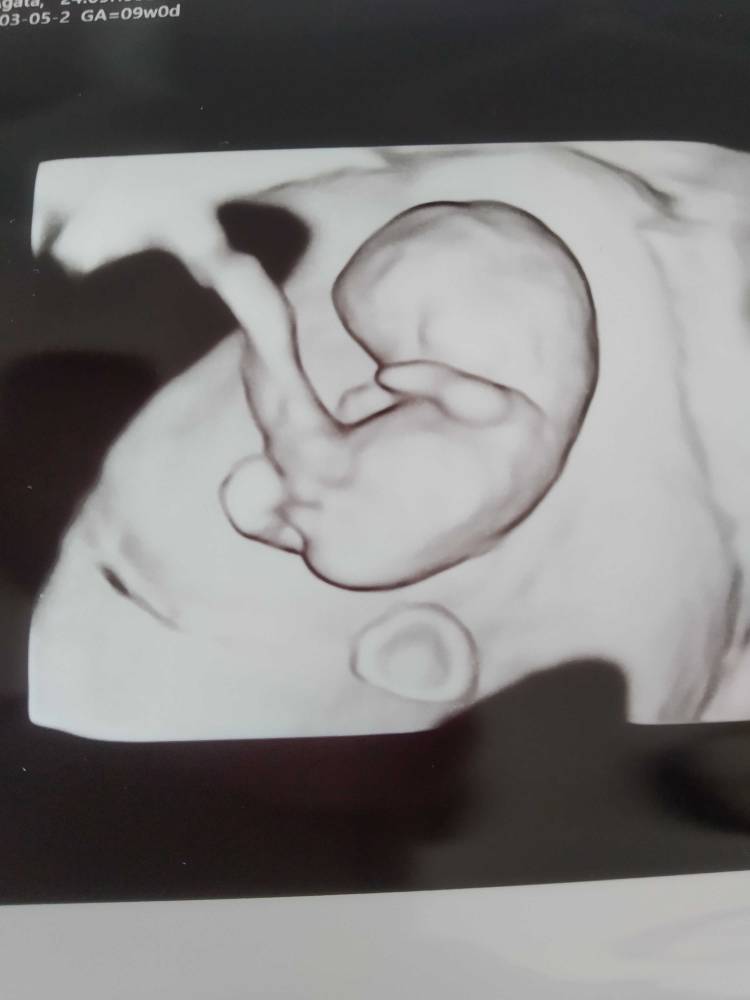

Dziewczyny w końcu dotarłam do domu. A wiec na dzień dzisiejszy wszystko jest dobrze. Maluszek ma nóżki i raczki, kręgosłup i szczękę - i oczywiście serduszko [emoji3059]

Po naciśnięciu ręka brzucha maluszek się ruszał a tak to spał.

Mamy 2,90cm i jest to 9+4 (wg om 9+5)

Termin porodu wpisany w zaświadczenie o ciąży 4.10.2020

A to nasz model/ka

Mój lekarz jest mistrzem USG i ma świetny sprzęt - Citomed w Toruniuza wizytę place 230 zł